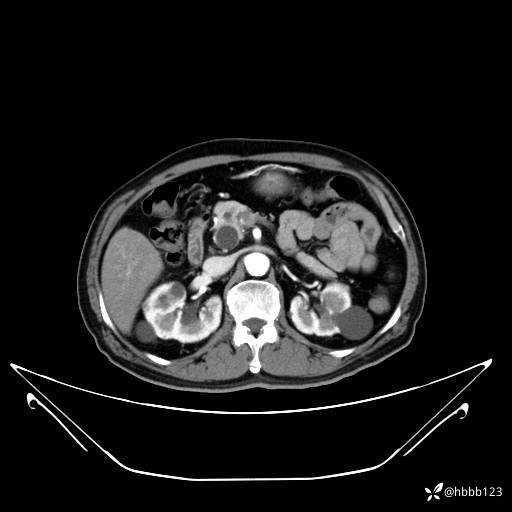

动脉期: